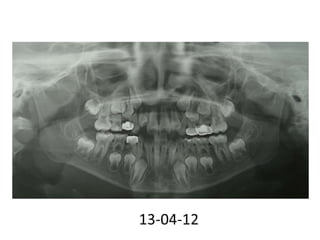

Caso clínico

Nombre: Vazquez Pacheco Luis

Edad:8 años

Expediente:431682

Diagnóstico: TDAH , Macrocefalia